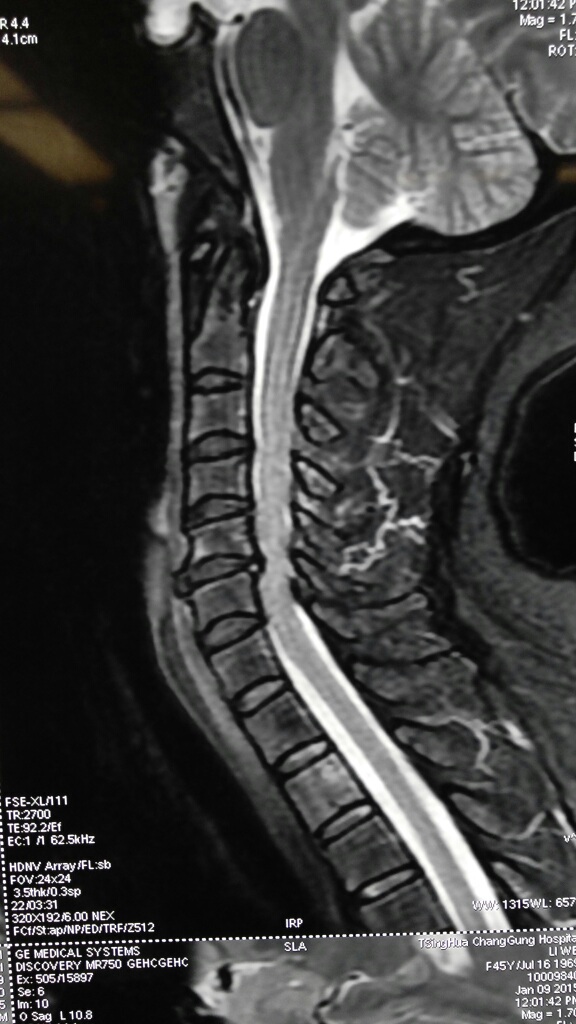

女性,46岁,主因“头晕,双上肢麻木,双下肢无力10余年"入院,颈椎MRI提示颈4-5,5-6,6-7椎间盘突出,5-6节段明显,骨质增生。

患者颈5-6突出明显,年龄尚年轻,可选择颈前路椎间盘切除,人工椎间盘植入术。